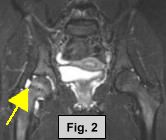

MRI FINDINGS:  The MRI was performed on AIC's high-field 1.5 Tesla short-bore Siemens Symphony.  Coronal T1 and fat suppressed turbo STIR weighted, axial proton density and T2 weighted with Fat Saturation, and sagittal DESS sequences were obtained bilaterally.  Fig. 1 (coronal T1W) shows widening and irregularity of the growth plate in the right hip.  Fig. 2 (coronal STIR) shows subtle adjacent marrow edema and moderate joint effusion.  Fig. 3 (sagittal DESS) and Fig. 4 (axial PD Fat Sat) also demonstrate the same findings.  Subtle medial displacement of the right femoral epiphysis is also noted on the coronal images.